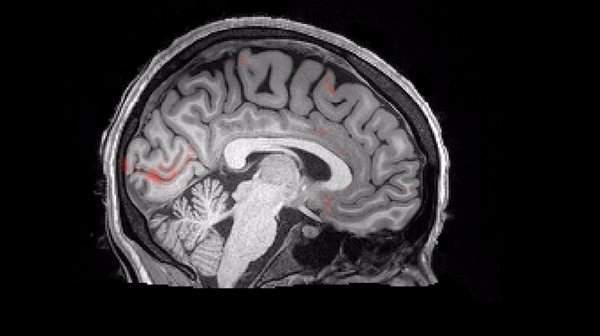

How memories are encoded, stored, and retrieved is the most intensively studied topic in neuroscience, and it is well established that a brain structure called the hippocampus plays a critical role in these processes.

That the hippocampus plays a critical role in memory has been known since the 1950s, from the pioneering studies of the famous amnesic patient H.M. More recently, advanced techniques have revealed that memories are encoded by the strengthening of specific synaptic connections within hippocampal circuits, and that their recall involves reactivation of these same circuits.

Examination of the animals’ brains revealed that this contextual fear conditioning activated neurons in the PFC, hippocampus, and amygdala, which together form a fear memory “engram.” Artificial activation of the PFC neurons alone induced recall of the fear engram, as evidenced by freezing behavior.